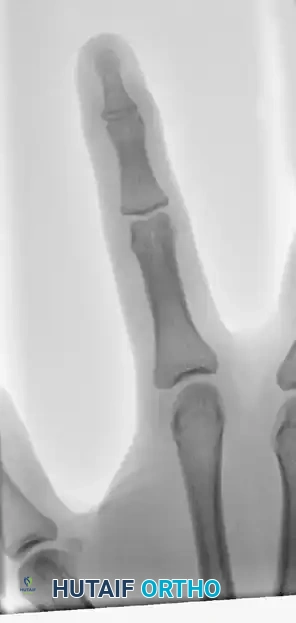

FIGURE 67-66 A: Type 4 bony mallet finger in a high-demand athlete, demonstrating a large dorsal fragment and volar subluxation of the distal phalanx.